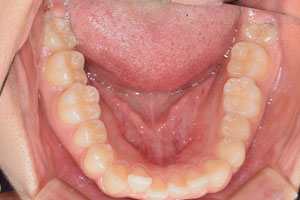

치료증례 전후사진

Before & After